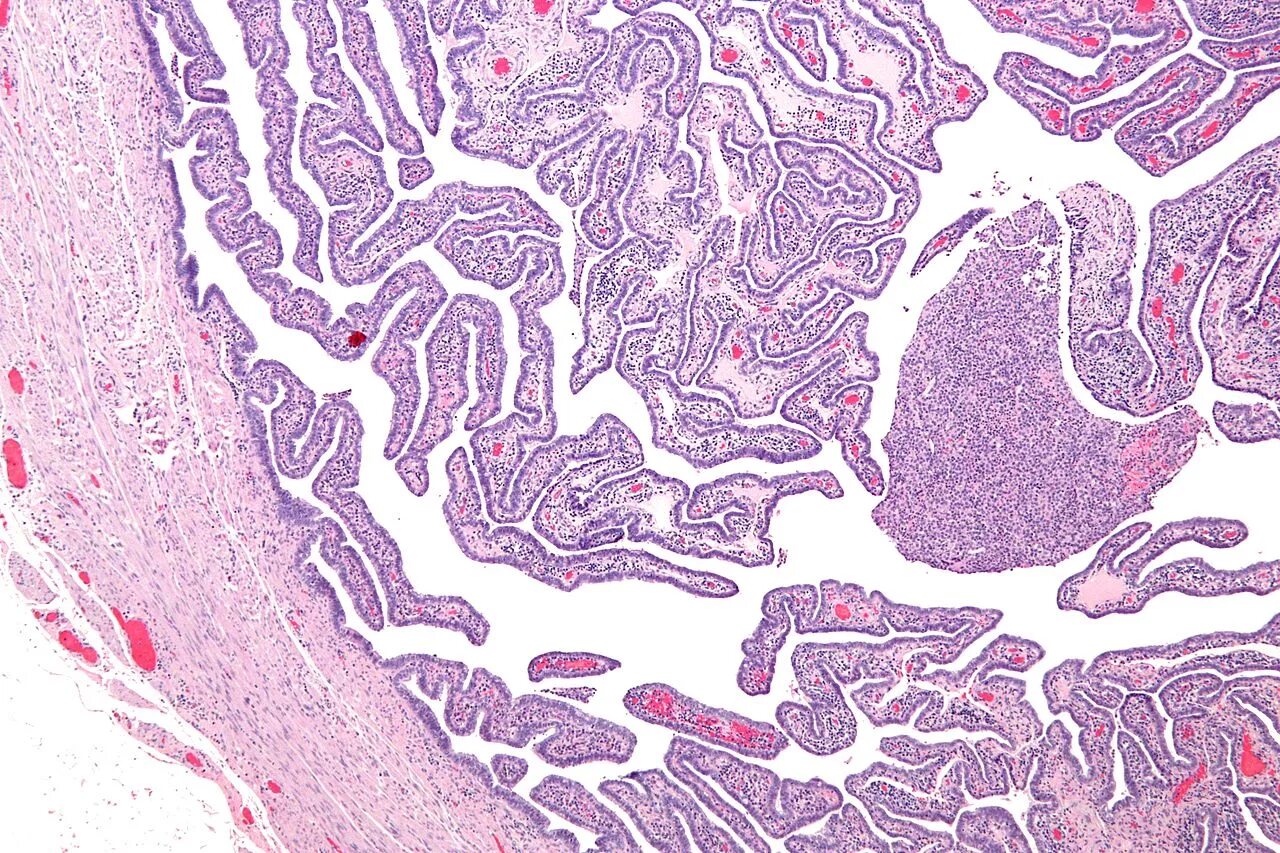

Маточная труба гистология